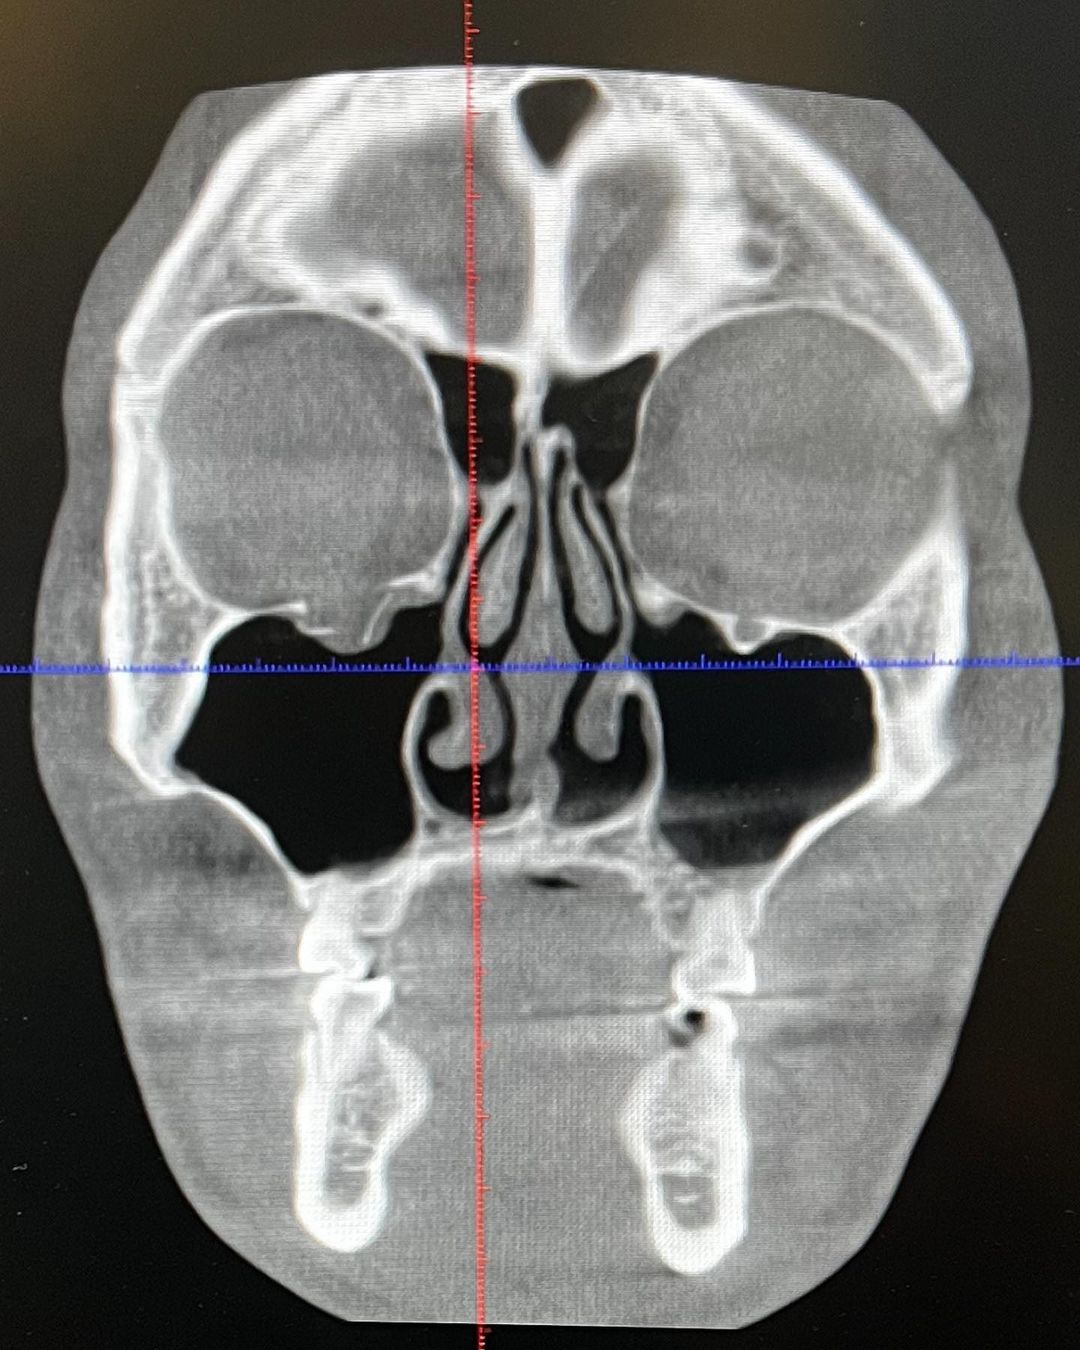

Since round 2, I was seeing triple vision because of this orbital fracture, I was facing three Cory in front of me. A titanium piece will put in for me next week, will come back tougher with the metal👊😼